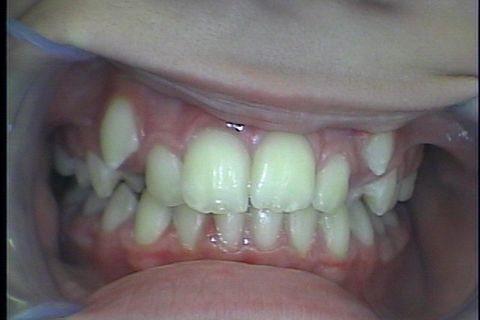

Fase final

Fase Final, intercuspidando e talvez haverá necessidade de desgastes interproximais devido a Bolton superior

Paciente Classe II, já havia usado disjuntor por falta de espaço, durante tratameto foi usado o Twin Force para projeção da arcada inferior e melhora do encaixe em Classe I de canino,na finalização do caso vemos que a paciente possui Bolton Superior o que provavelmente gerará a necessidade de desgastes interproximais para concluirmos com uma finalização adequada do caso.